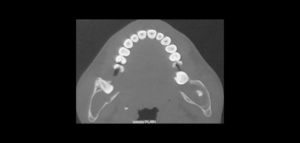

132 – Tratamiento de la reabsorción radicular interna idiopática perforante: controles radiográficos

La reabsorción radicular interna (RRI) es una afección inflamatoria que resulta en la destrucción progresiva de la dentina intra-radicular a lo largo de los tercios